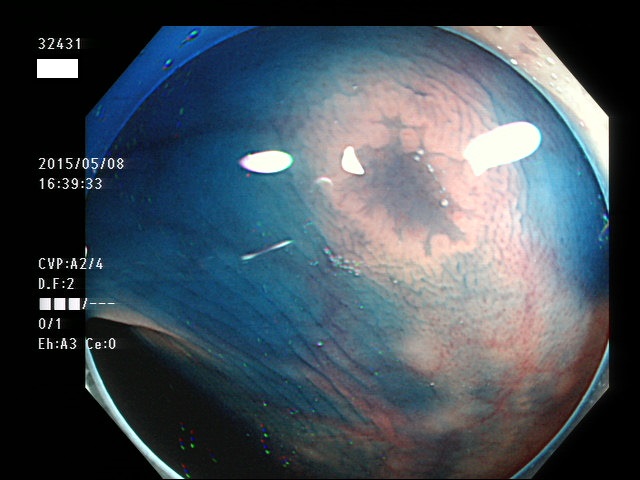

上記100名より抽出した平坦・陥凹型腺腫(=癌化の危険が高いが見落としやすい病変)の内視鏡写真